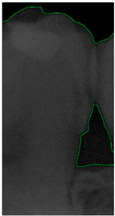

Figure 8.

Image-enhancement results: (a) binarization; (b) mathematical morphology; (c) added green line represents canny; (d) overlap onto the original image.

2.3.4. Mathematical Morphology

2.3.5. Canny Edge Detection

Since filtered and binarized images alone cannot enhance the features of dental calculus, this approach does not effectively improve the accuracy of machine learning. Therefore, this study employed edge detection to identify the contours of tooth edges, enhancing the regions of interest and thereby improving the accuracy of machine learning. The canny edge-detection algorithm applies non-maximum suppression to each pixel, retaining pixels with local maximum gradient values, which can produce continuous and accurate edges while demonstrating good resistance to noise. The edge-detection results are represented in green, as shown in Figure 8c. Finally, these results are overlaid back onto the original image, as illustrated in Figure 8d.